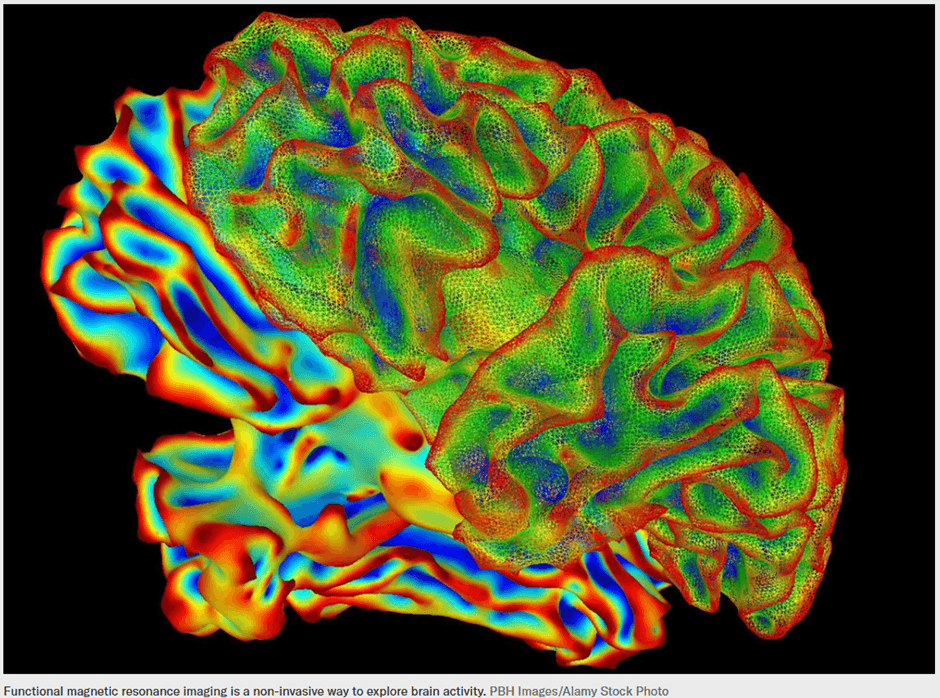

For decades, neuroscientists have attempted to peer into the brain and translate neural activity into understandable signals. While earlier research could roughly predict what a person was seeing or hearing, converting rich mental experiences into coherent language remained beyond reach. The gap between raw brain signals and meaningful sentences seemed too wide to bridge.

First, researchers used a deep-language model to analyze captions from more than 2,000 videos. Each caption was converted into a numerical representation, or meaning signature, capturing its semantic content rather than its exact wording. In parallel, a second AI model was trained on functional MRI data collected while participants watched these videos. This model learned to associate specific patterns of brain activity with the corresponding meaning signatures.